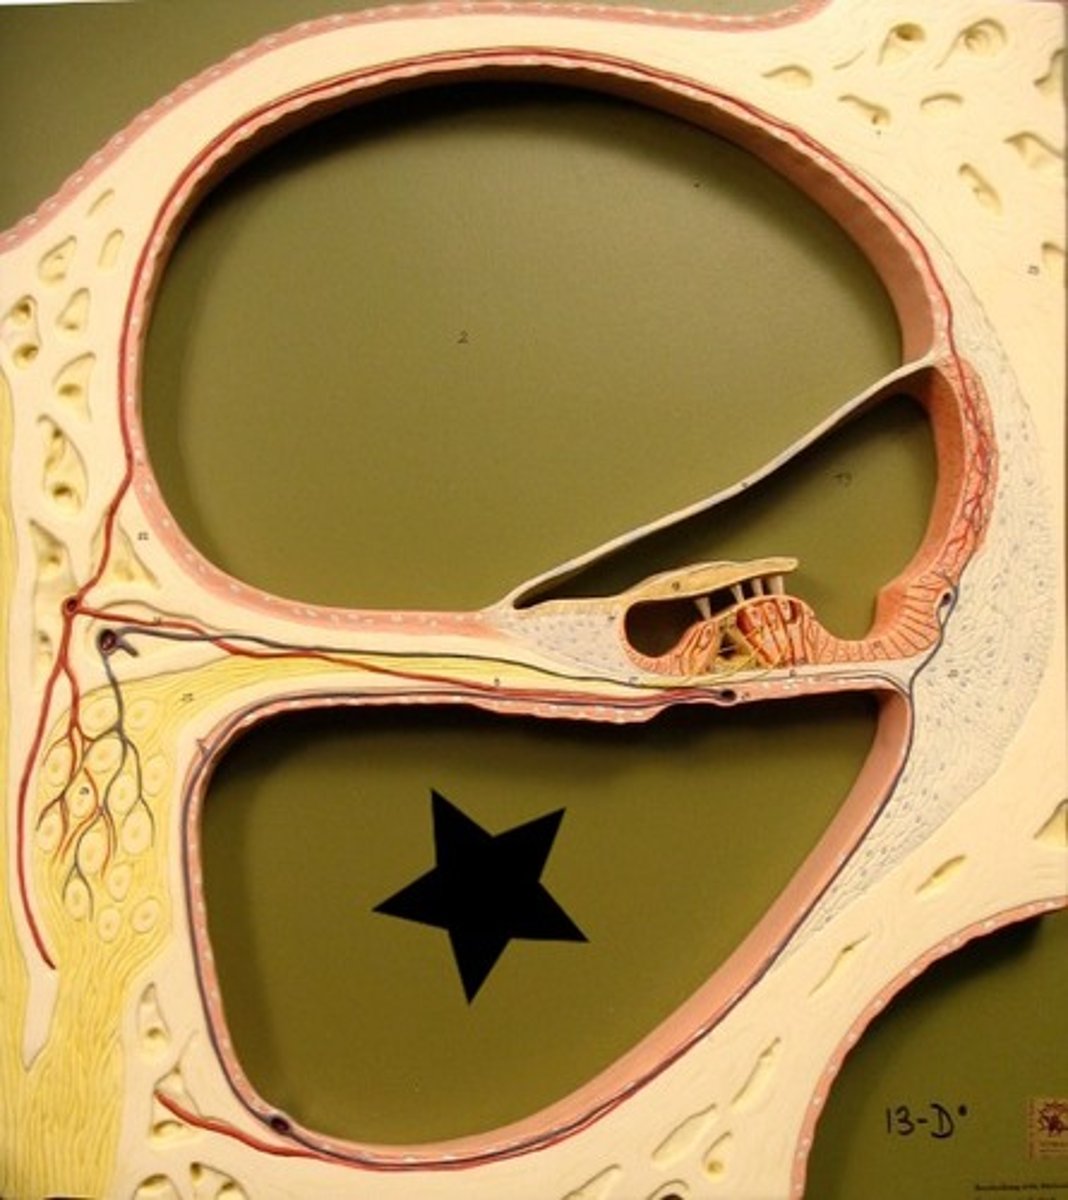

auditory tube

auricle (pinna)

cochlea

cochlear nerve

external auditory canal

incus

labyrinth (osseous + membranous)

malleus

oval window

round window

scala tympani

section of cochlea

scala vestibuli

section of cochlea

semicircular canals

spiral organ (of corti)

section of cochlea

stapes

temporal bone

tympanic membrane

vestibular nerve

vestibule

vestibulocochlear nerve